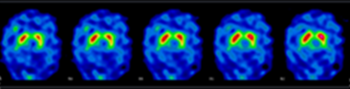

Exemples d’images obtenues par le service de Médecine Nucléaire de l’hôpital de Citadelle

• Neurologie nucléaire : examens spécialisés (Datscan, HMPAO, MIBG, FDG, …)